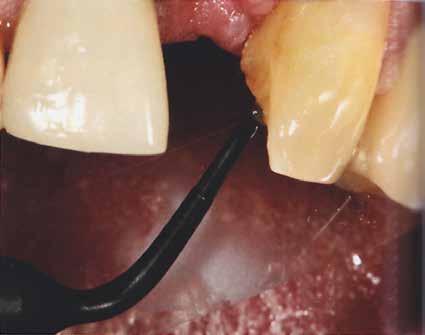

Az egyszárnyú ragasztott híd mellett döntöttünk (1. a kép)

Mivel a szemfogak általában nagyon közel vannak az antagonistához, kettes pótlására a szárnyat inkább a nagymetszőre szoktuk tervezni. Ehhez persze invazív preparációra van szükség – érintetlen fogak esetén ez lehetőleg kerülendő.

A bemutatott esetben azonban könnyen döntöttünk, mivel a szemfog disztális részén nagy tömés volt. A defektust bevontuk az eset megoldásába.

A preparálást követően Provil-lal vettünk lenyomatot.

A laboratóriumban szekciós minta készült, blokk-stiftekkel (1. kép) , amelynek készítése során nagy figyelmet szenteltünk az ínymaszk (Majesthetik- Gingiimplant picodent) és a felfekvő lengőtag területének (2–6. képek)